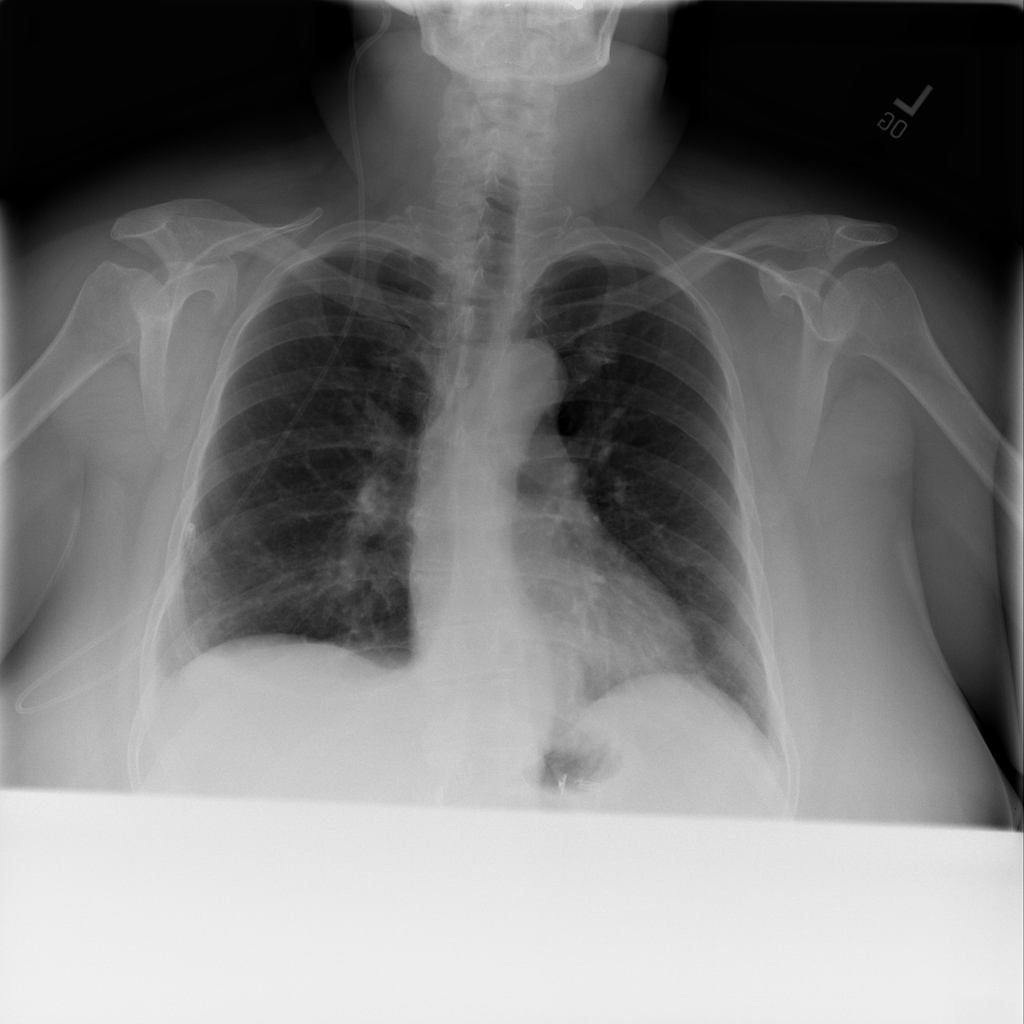

PAT-4639 · IMG-021Effusion

PAT-4639 · IMG-021

PA